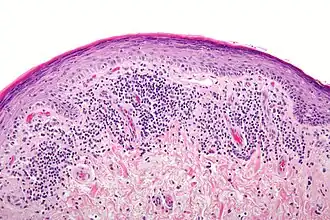

Histología

Se requieren 3 criterios histológicos para diagnosticar LPO:

- Que no haya signos de displasia.

- Degeneración hidrópica de la lámina basal celular.

- Infiltración de células de la inflamación a la capa subepitelial del tejido conjuntivo.